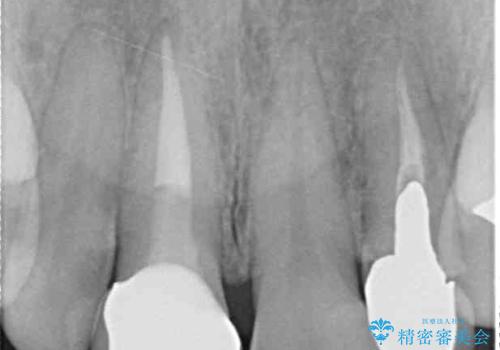

- 保険診療でのクラウンが変色してしまったとのことで来院された患者様です。

根管治療がされていなかったため、まずは根管治療を行い、その後オールセラミッククラウンにて補綴することとしました。